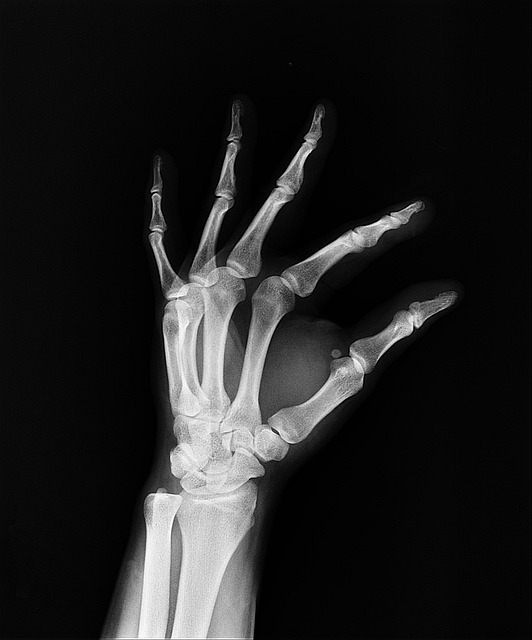

골다공증의 원인을 알아보자. 우리의 뼈는 태아 때부터 계속 자라고 굵어져서 35세가 되면 골농도가 가장 높아지고 그 후 계속적으로 골농도가 감소한다. 여성들은 폐경이 된 후부터 급작스런 골농도의 감소에 따라 쉽게 골절이 되고 뼈에 구멍이 많아지는 골다공증이 발생한다. 골다공증에 걸리게 되면 골질량이 매우 적어져서 외부의 조그만 충격도 아기지 못하고 쉽게 뿌러지고 만다. 골다공증의 종류에는 1차적 골다공증과 2차적 골다공증이 있다.

골다공증의 증상, 골다공증은 50세를 전후한 폐경기와 관련된 제1형 폐경기성 골다공증과 65세 이후에 발생되는 제2형 노인성 골다공증으로 구분한다. 제1형 골다공즈은 에스트로겐으로 치료가 가능하다. 발생 확률은 나이가 많고 여성을 제외하고도 근육과 지방질이 없는 사람 ,칼슘과 운동부족인 사람에게 발생률이 높다. 골절이 일어날 때까지는 별 자각증세가 나타나지 않는다. 또 골절이 되더라도 증상이 없는 경우가 대부분이며 약간의 경우 요통이 나타나기도 한다. 골다공증이 생기면 팔의 상박부 골절, 고관절 골절, 척추뼈의 압박골절이 잘 생긴다. 허리를 구부리거나 주저앉는 등 사소한 충격으로도 골절될 수 있다.